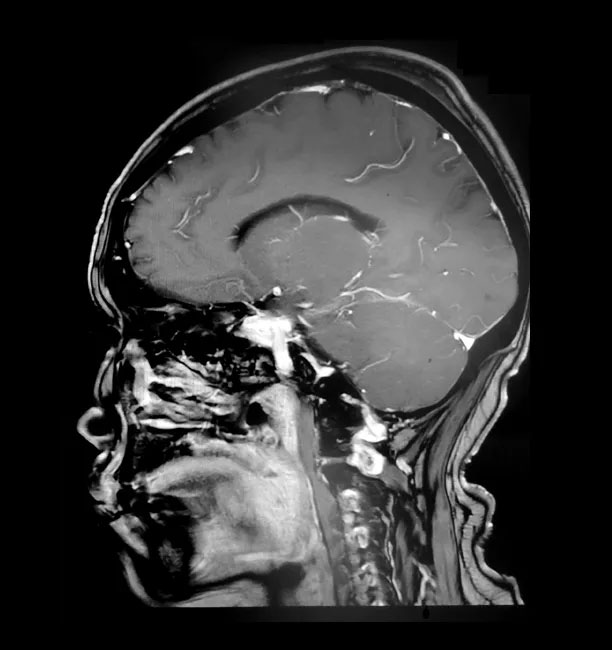

▲ 术后影像显示,肿瘤已被切除

术后一周,胡女士恢复情况良好,没有出现偏瘫失明等功能障碍和其他明显并发症。